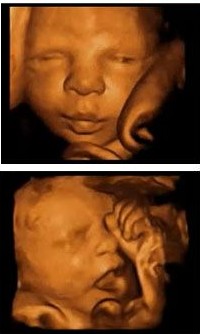

四维彩超,全称为四维彩色超声诊断仪,是上先进的彩色超声设备。四维彩超对准妈妈来说,其实是颗“定心丸”,因为它能够多方位、多角度地观察宫内胎儿的生长发育情况,为早期诊断胎儿先天性体表畸形和先天性心脏疾病提供准确的科学依据。而且对孕妇、胎儿等人群造成任何损伤和导致胎儿发育不良和伤残。更重要的是四维彩超还十分的经济实惠。

1、四维彩超系统超越了二维、三维超声的限制,不仅能够检查胎儿的生理指标,还使堆枯燥难懂的B超数据结果,变成清晰的动态图像可对胎儿的体格、健康发育状况进行检查,为早期诊断各种胎儿先天性体表畸形和先天性心脏疾病等提供准确全面的科学依据,让待产准妈妈们安心,家人放心!

2、显示结果直观,易于理解,便于准父母们对图像的认识和理解,也便于对胎儿病变和畸形的认识和理解,便于医生与准父母们的沟通。

4、能亲眼目睹胎儿在准妈妈肚子里的各种生理活动,增进准父母与胎儿的情感交流。